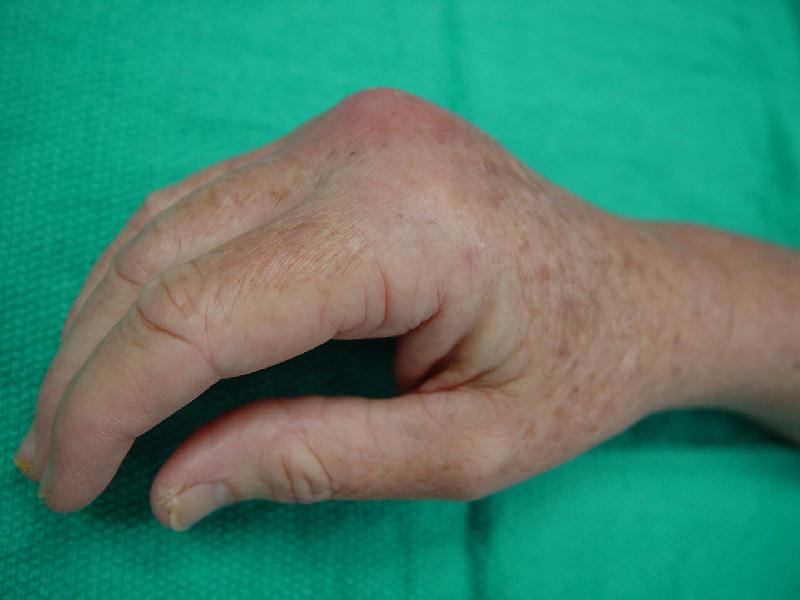

Cat bite injury, 2 days old, extensor tendon and metacarpophalangeal joint involvement, treated with radical excisional debridement and sealed continuous irrigation/suction. Extensor lag treated with "hammock" splint.